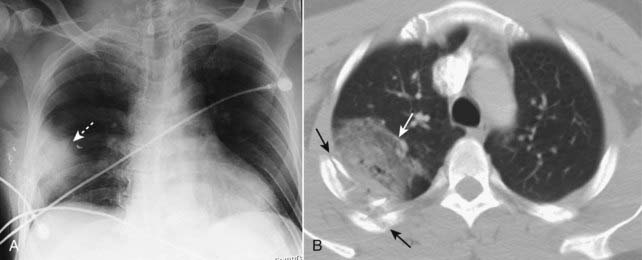

image

Figure 17-4 Pulmonary lacerations, conventional radiograph, and CT.

Lacerations are sometimes masked, at least for the first few days, by the airspace disease in a surrounding pulmonary contusion. A, If they are completely filled with blood, they will appear as an ovoid mass (dotted white arrow). B, If they are partially filled with blood and partially filled with air, they may contain a visible air-fluid level (solid black arrow). Unlike the neighboring pulmonary contusion (solid white arrow), pulmonary lacerations, especially if they are blood filled, may take weeks or months to completely clear. The top of the left hemidiaphragm (D) is seen in this image.